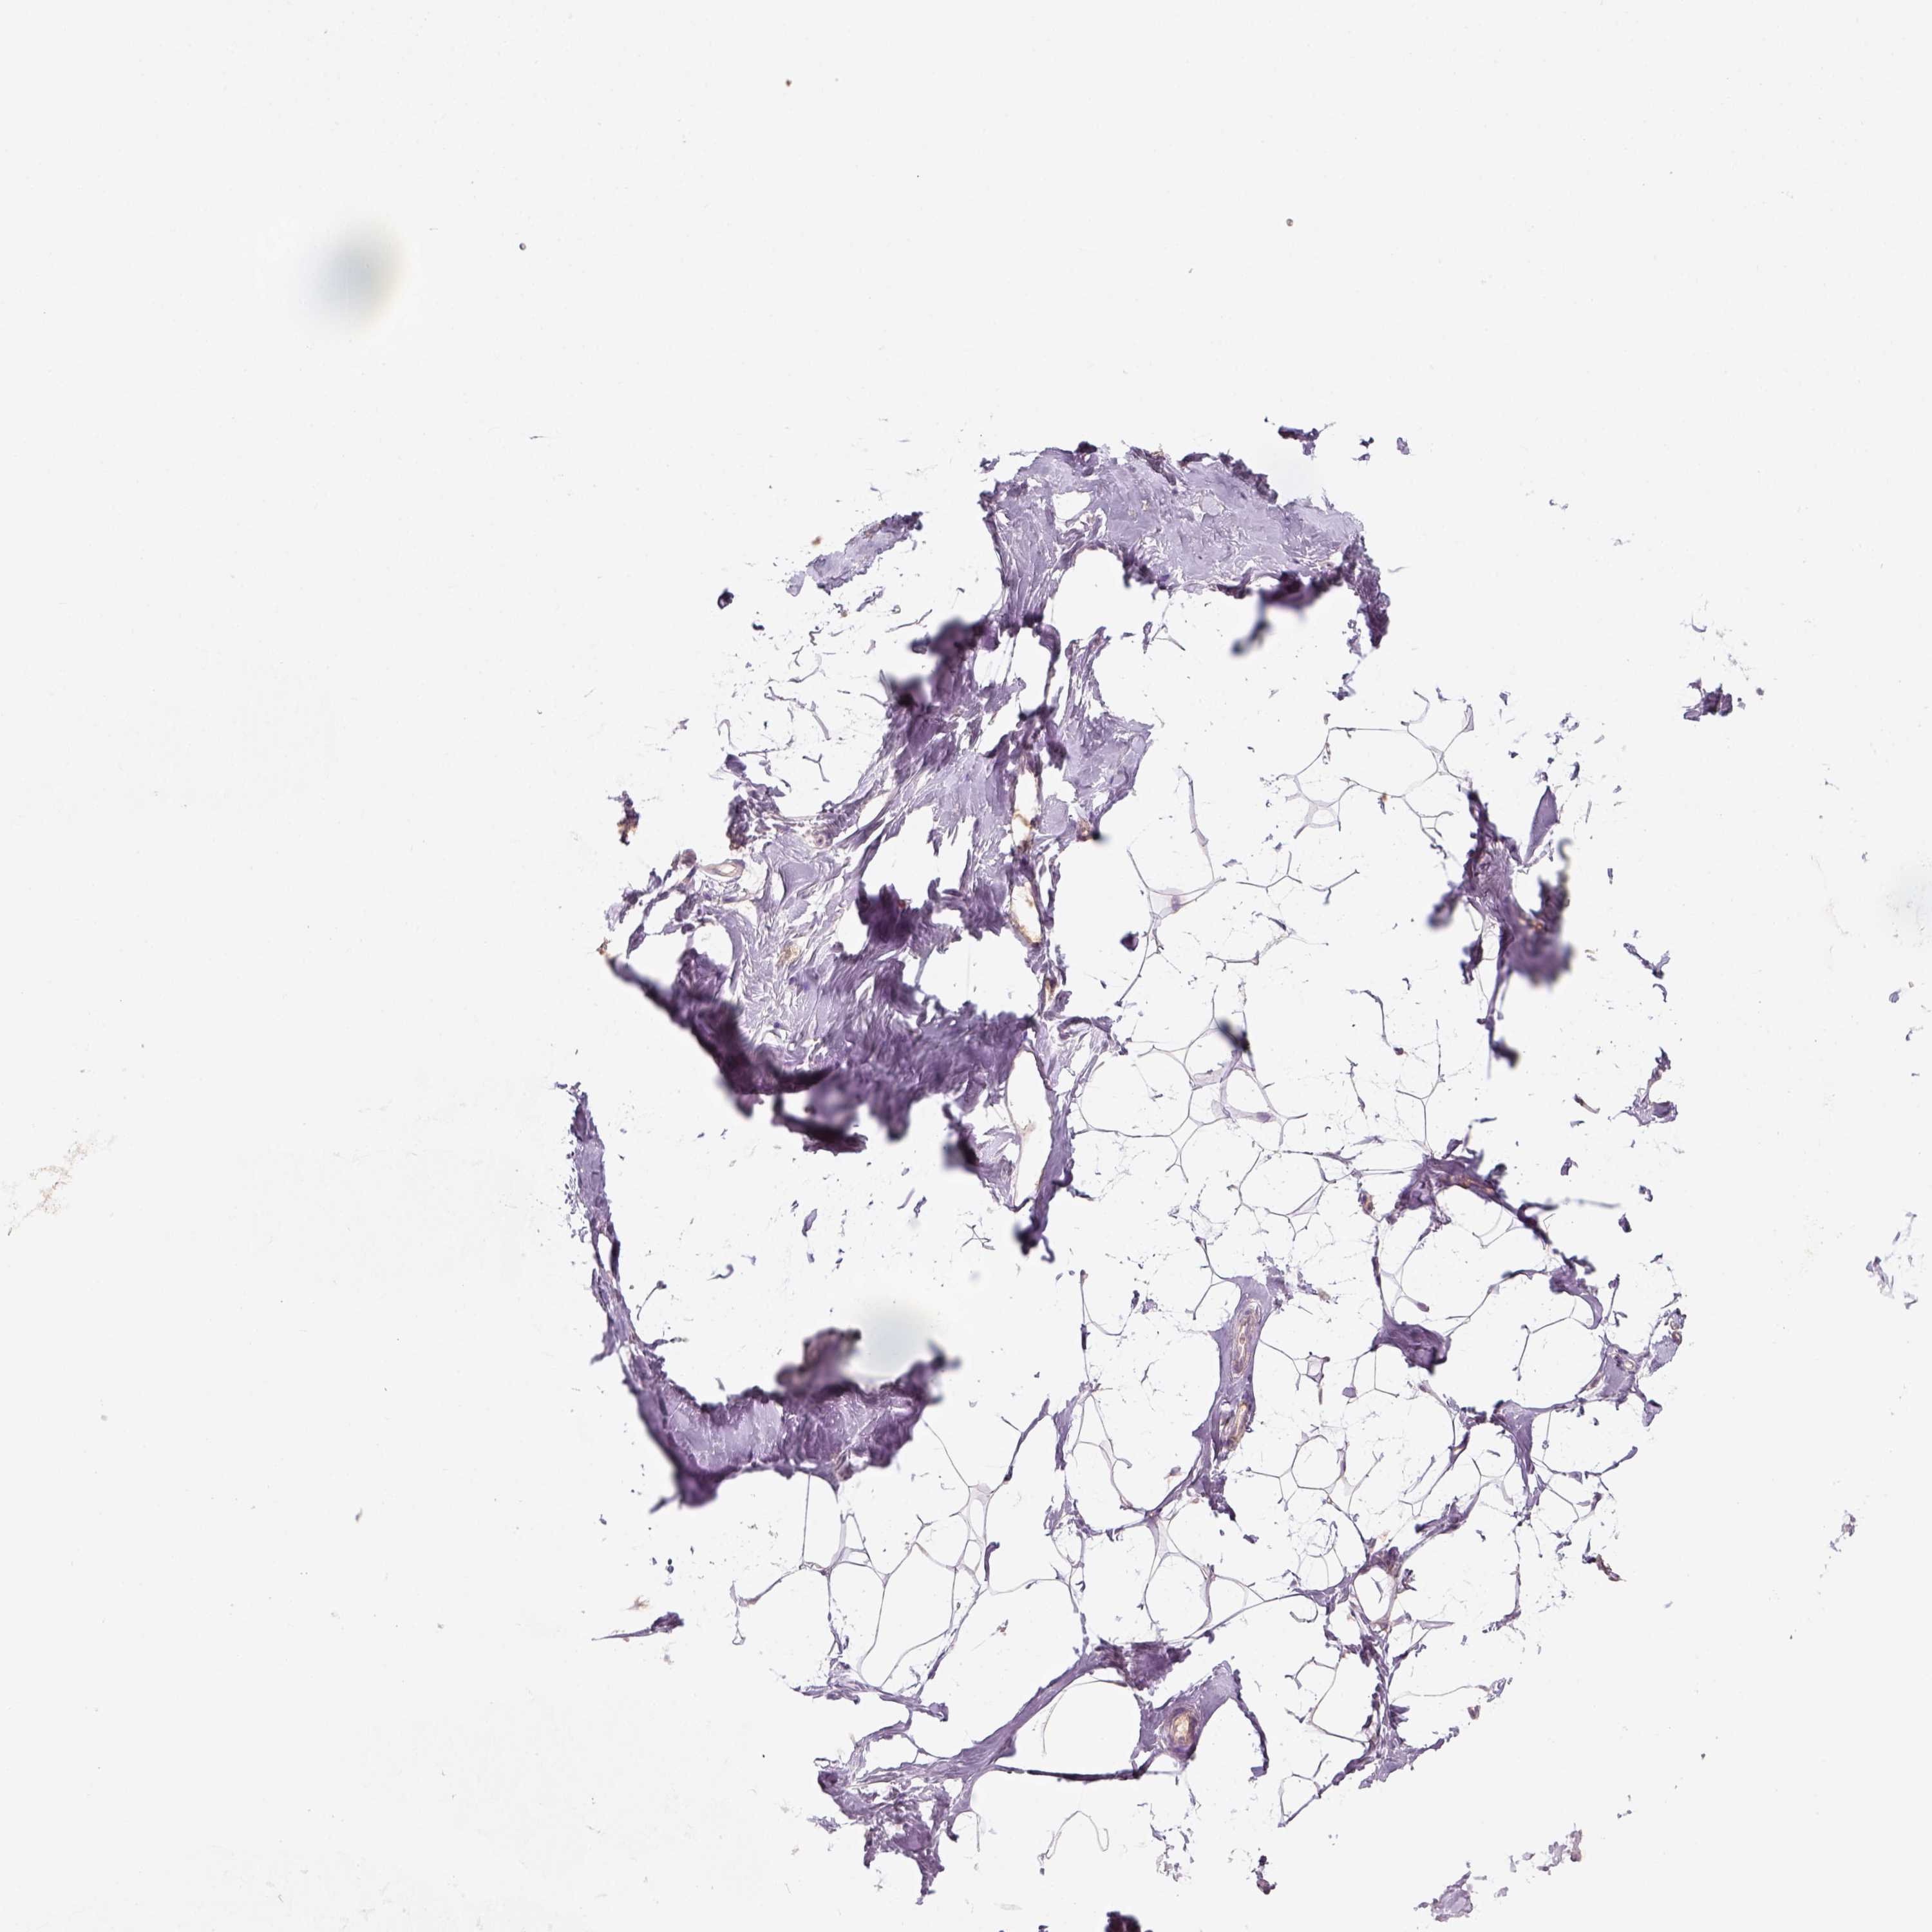

TISSUE PRIMARY DATA BREAST Show tissue menu

Breast

BREAST - Antibody stainingi

Antibody staining in the annotated cell types in the current human tissue is reported as not detected, low, medium, or high, based on conventional immunohistochemistry profiling in selected tissues. This score is based on the combination of the staining intensity and fraction of stained cells.

Each image is clickable and will lead to virtual microscopy that enables deeper exploration of all samples and also displays staining intensity scores, fraction scores and subcellular localization as well as patient and tissue information for each sample.

Antibody HPA074762Antibody CAB075684

Adipocytes Not detectedNot detected

Glandular cells Not detectedNot detected

Myoepithelial cells Not detectedNot detected